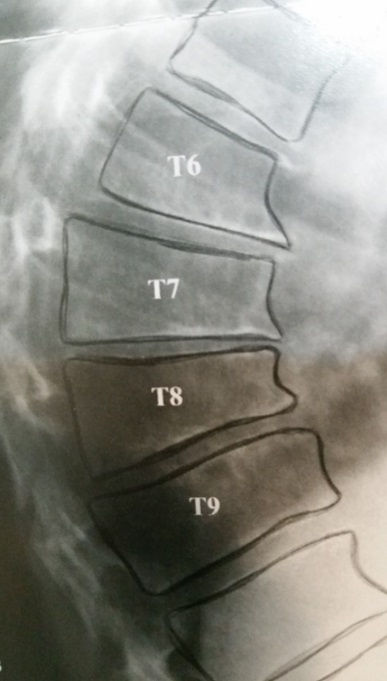

Tipicamente localiza-se na coluna torácica média e o seu ápice encontra-se entre a sétima(T7) e a nona vértebra(T9).

Imagem radiológica típica da cifose rígida do adolescente.

Alterações morfológicas das vértebras torácicas - acunhamento.